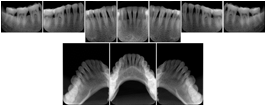

3. A dental provider wishes to capture a series of DICOM IO images for the patient’s dentition. The tooth morphology, teeth are divided into molars, premolars, canines and incisors, and a number of images for each jaw. The anatomic information was captured utilizing the triplet of schema. This standard code sequence is based on ISO 3950-2010, Dentistry - Designation system for teeth and areas of the oral cavity.

Every IO image should have anatomic information either through the primary or modifier sequence.

In most standard cases, images are oriented in structured layouts. These structured displays are useful to be shared between providers for reference purposes.

Table OO.1.1-1 shows structured display standard templates, where Viewset ID is based on the Japanese Society for Oral and Maxillofacial Radiology (JSOMR) classification provided by JIRA (Japan Medical Imaging and Radiological Systems Industries Association, www.jira-net.or.jp). Expected or typical teeth to be imaged location, region and designation codes are based on ISO 3950-2010, Dentistry - Designation system for teeth and areas of the oral cavity. For all the hanging protocols listed in OO.1.1-1, the value to use for Hanging Protocol Creator (0072,0008) is "JSOMR" and the value to use for Hanging Protocol Name (0072,0002) does not include "JSOMR" (e.g., "DL-S001A", not "JSOMR DL-S001A").